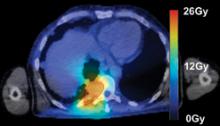

Radiation therapy is an important clinical option for the alleviation of pain and suffering for cancer patients and is used for palliative treatments to prevent pathologic bone fractures or tumor-induced obstructions, bleeding and pain that is resistant to other treatments.

However, standard palliative radiation therapy treatment techniques often offer poor conformality and expose large volumes of normal tissues to radiation-induced toxicities, causing significant side effects for an already ill patient with a limited life expectancy.

Treatment planning is a critical component of a patient’s road toward an optimal outcome when dealing with cancer. Whether the ultimate goal is palliative or a total cure, treatment planning always aims to provide just enough dose to a targeted area to eradicate the cancer, while sparing nearby tissue or organs.